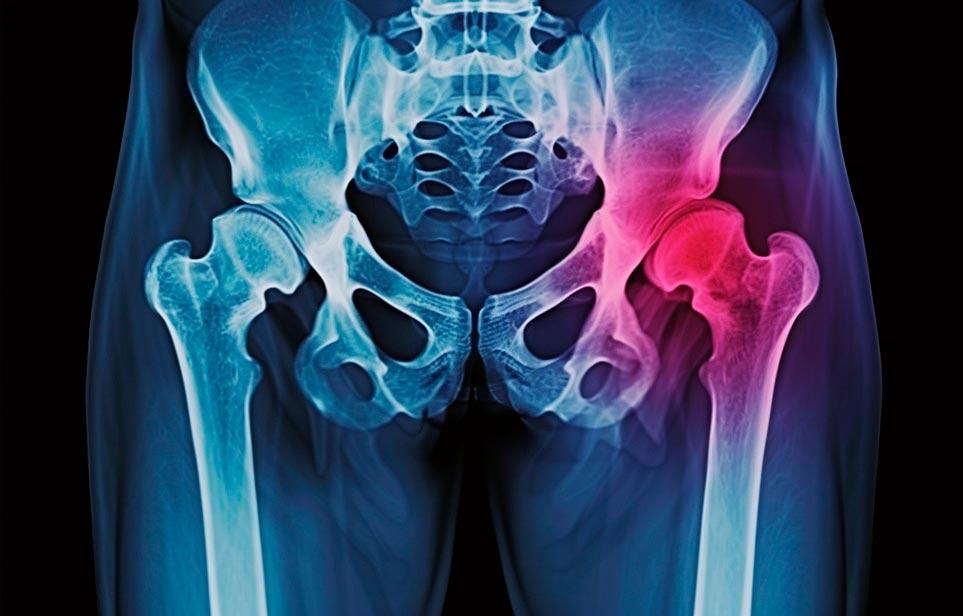

Реабилитация пожилых после перелома шейки бедра в Екатеринбурге

Эффективная и профессиональная реабилитация после перелома шейки бедра в Екатеринбурге осуществляется по демократичным ценам лучшими специалистами современной медицинской клиники «Заботливые люди» с применением персонального подхода к каждому пожилому человеку с такой тяжёлой травмой бедренной кости ноги. В процессе осуществления такой специализированной услуги все наши пациенты имеют возможность получения качественного и достойного обслуживания, эффективного восстановления. Лучший дом престарелых позаботиться о Вашем близком человеке.

Такая травма в большей части случаев возникает у граждан преклонного возраста. При её появлении на протяжении длительного времени сохраняются болевые и неприятные ощущения в области паха, при которых серьёзно ухудшается качество жизни, возникает множество последствий для его жизни и здоровья.

По какой симптоматике можно определить перелом шейки бедра

- Визуально повреждённая нога сокращается на несколько сантиметром из-за сокращения мышц.

- Стопа выворачивается наружу.

- В лежачем положении человек не может поднять ногу.

При такой симптоматике важно незамедлительно обращаться к специалистам для получения всей необходимой помощи, терапии и восстановления после перелома шейки бедра. Если не оказать помощи старику, то это приведёт к гноению, инвалидности, иным видам осложнений.